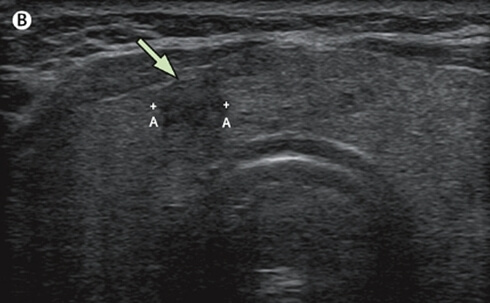

갑상선 유두암은 갑상선에 발생하는 몇 가지 암들 중에서 고주파 치료를 해볼 만한 암입니다. 갑상선 유두암 중에서도 크기가 1cm 이하인 유두암을 미세유두암이라고 부릅니다.

그리고 갑상선 미세유두암 중에서도 피막침범이 없고, 림프절 전이가 없으며, 타 장기로 원격 전이가 되지 않은 미세유두암을 저위험군 미세유두암이라고 부릅니다.

이러한 미세유두암부터가 고주파 절제술의 대상입니다. 최근에 나오는 갑상선 미세유두움 고주파 치료의 많은 연구 결과들을 보면 대게 저위험군 미세유두암 환자들을 대상으로 치료를 했습니다.